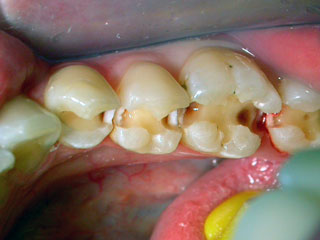

Tiefe Karies an vielen Zähnen

erkennbar an den braunen Stellen mit weißlicher Umrahmung